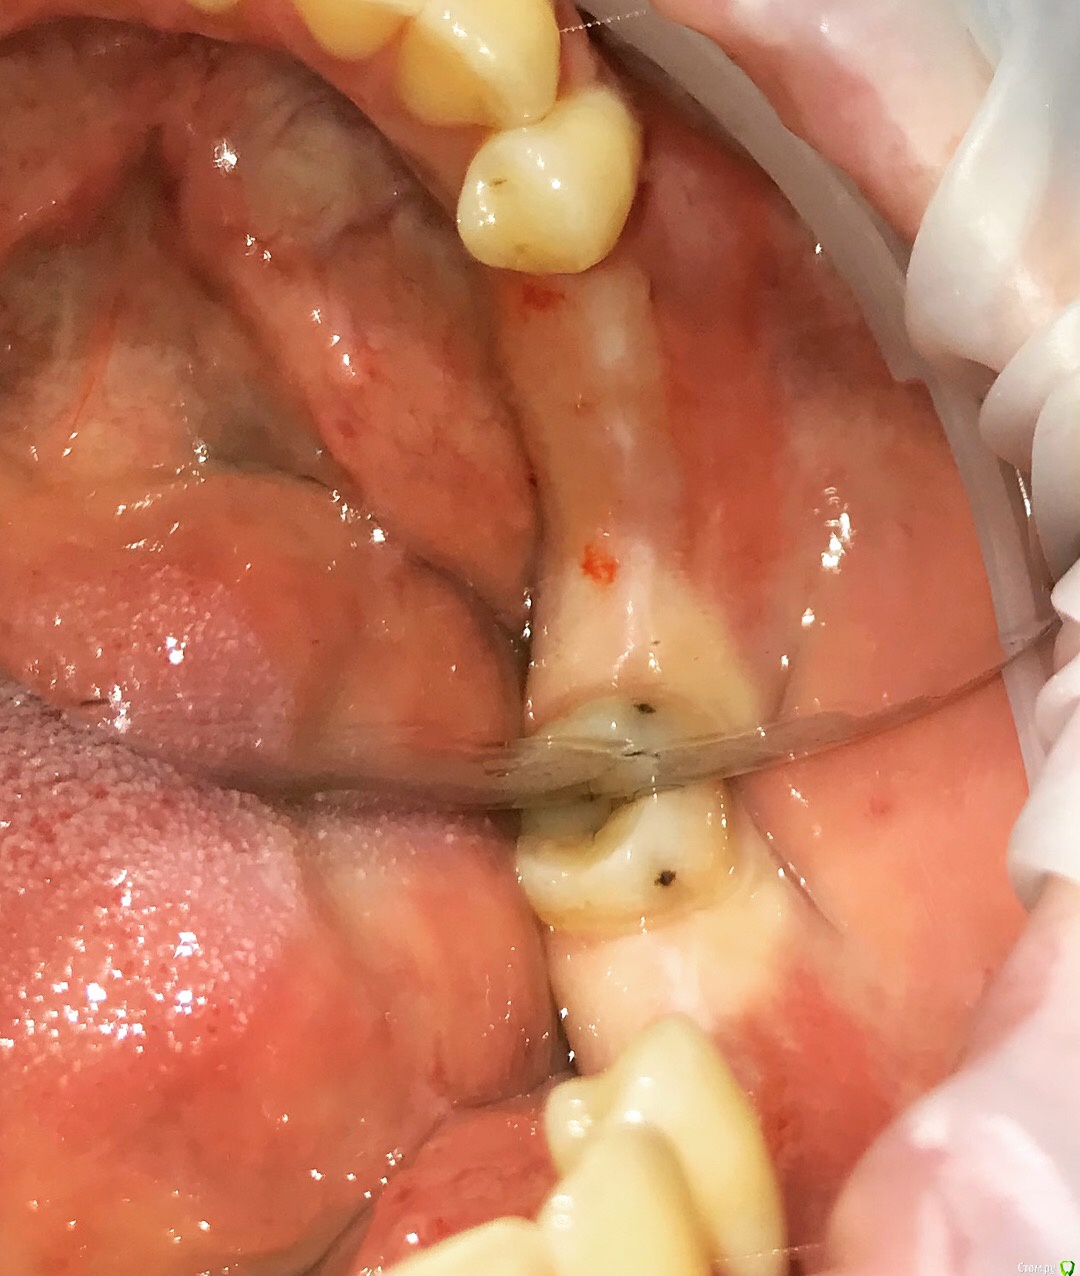

Santi Опубликовано 15 октября, 2018 Автор Поделиться Опубликовано 15 октября, 2018 Результат после пары недель на времяшках. Доктора, если бы не делали ССТ получился бы такой профиль Пы Сы, биполярка залагала, работает только одна вспышка, за качество сорри )) 1 Ссылка на комментарий

Santi Опубликовано 15 октября, 2018 Автор Поделиться Опубликовано 15 октября, 2018 (изменено) Да а высота десны? особенно в промежуточной зоне Изменено 15 октября, 2018 пользователем Santi Ссылка на комментарий

АнтонТЛТ Опубликовано 15 октября, 2018 Поделиться Опубликовано 15 октября, 2018 а высота десны? особенно в промежуточной зонеПеред фиксацией временного протеза, делается разрез между имплантатами и овоид погружается в него. 2 Ссылка на комментарий